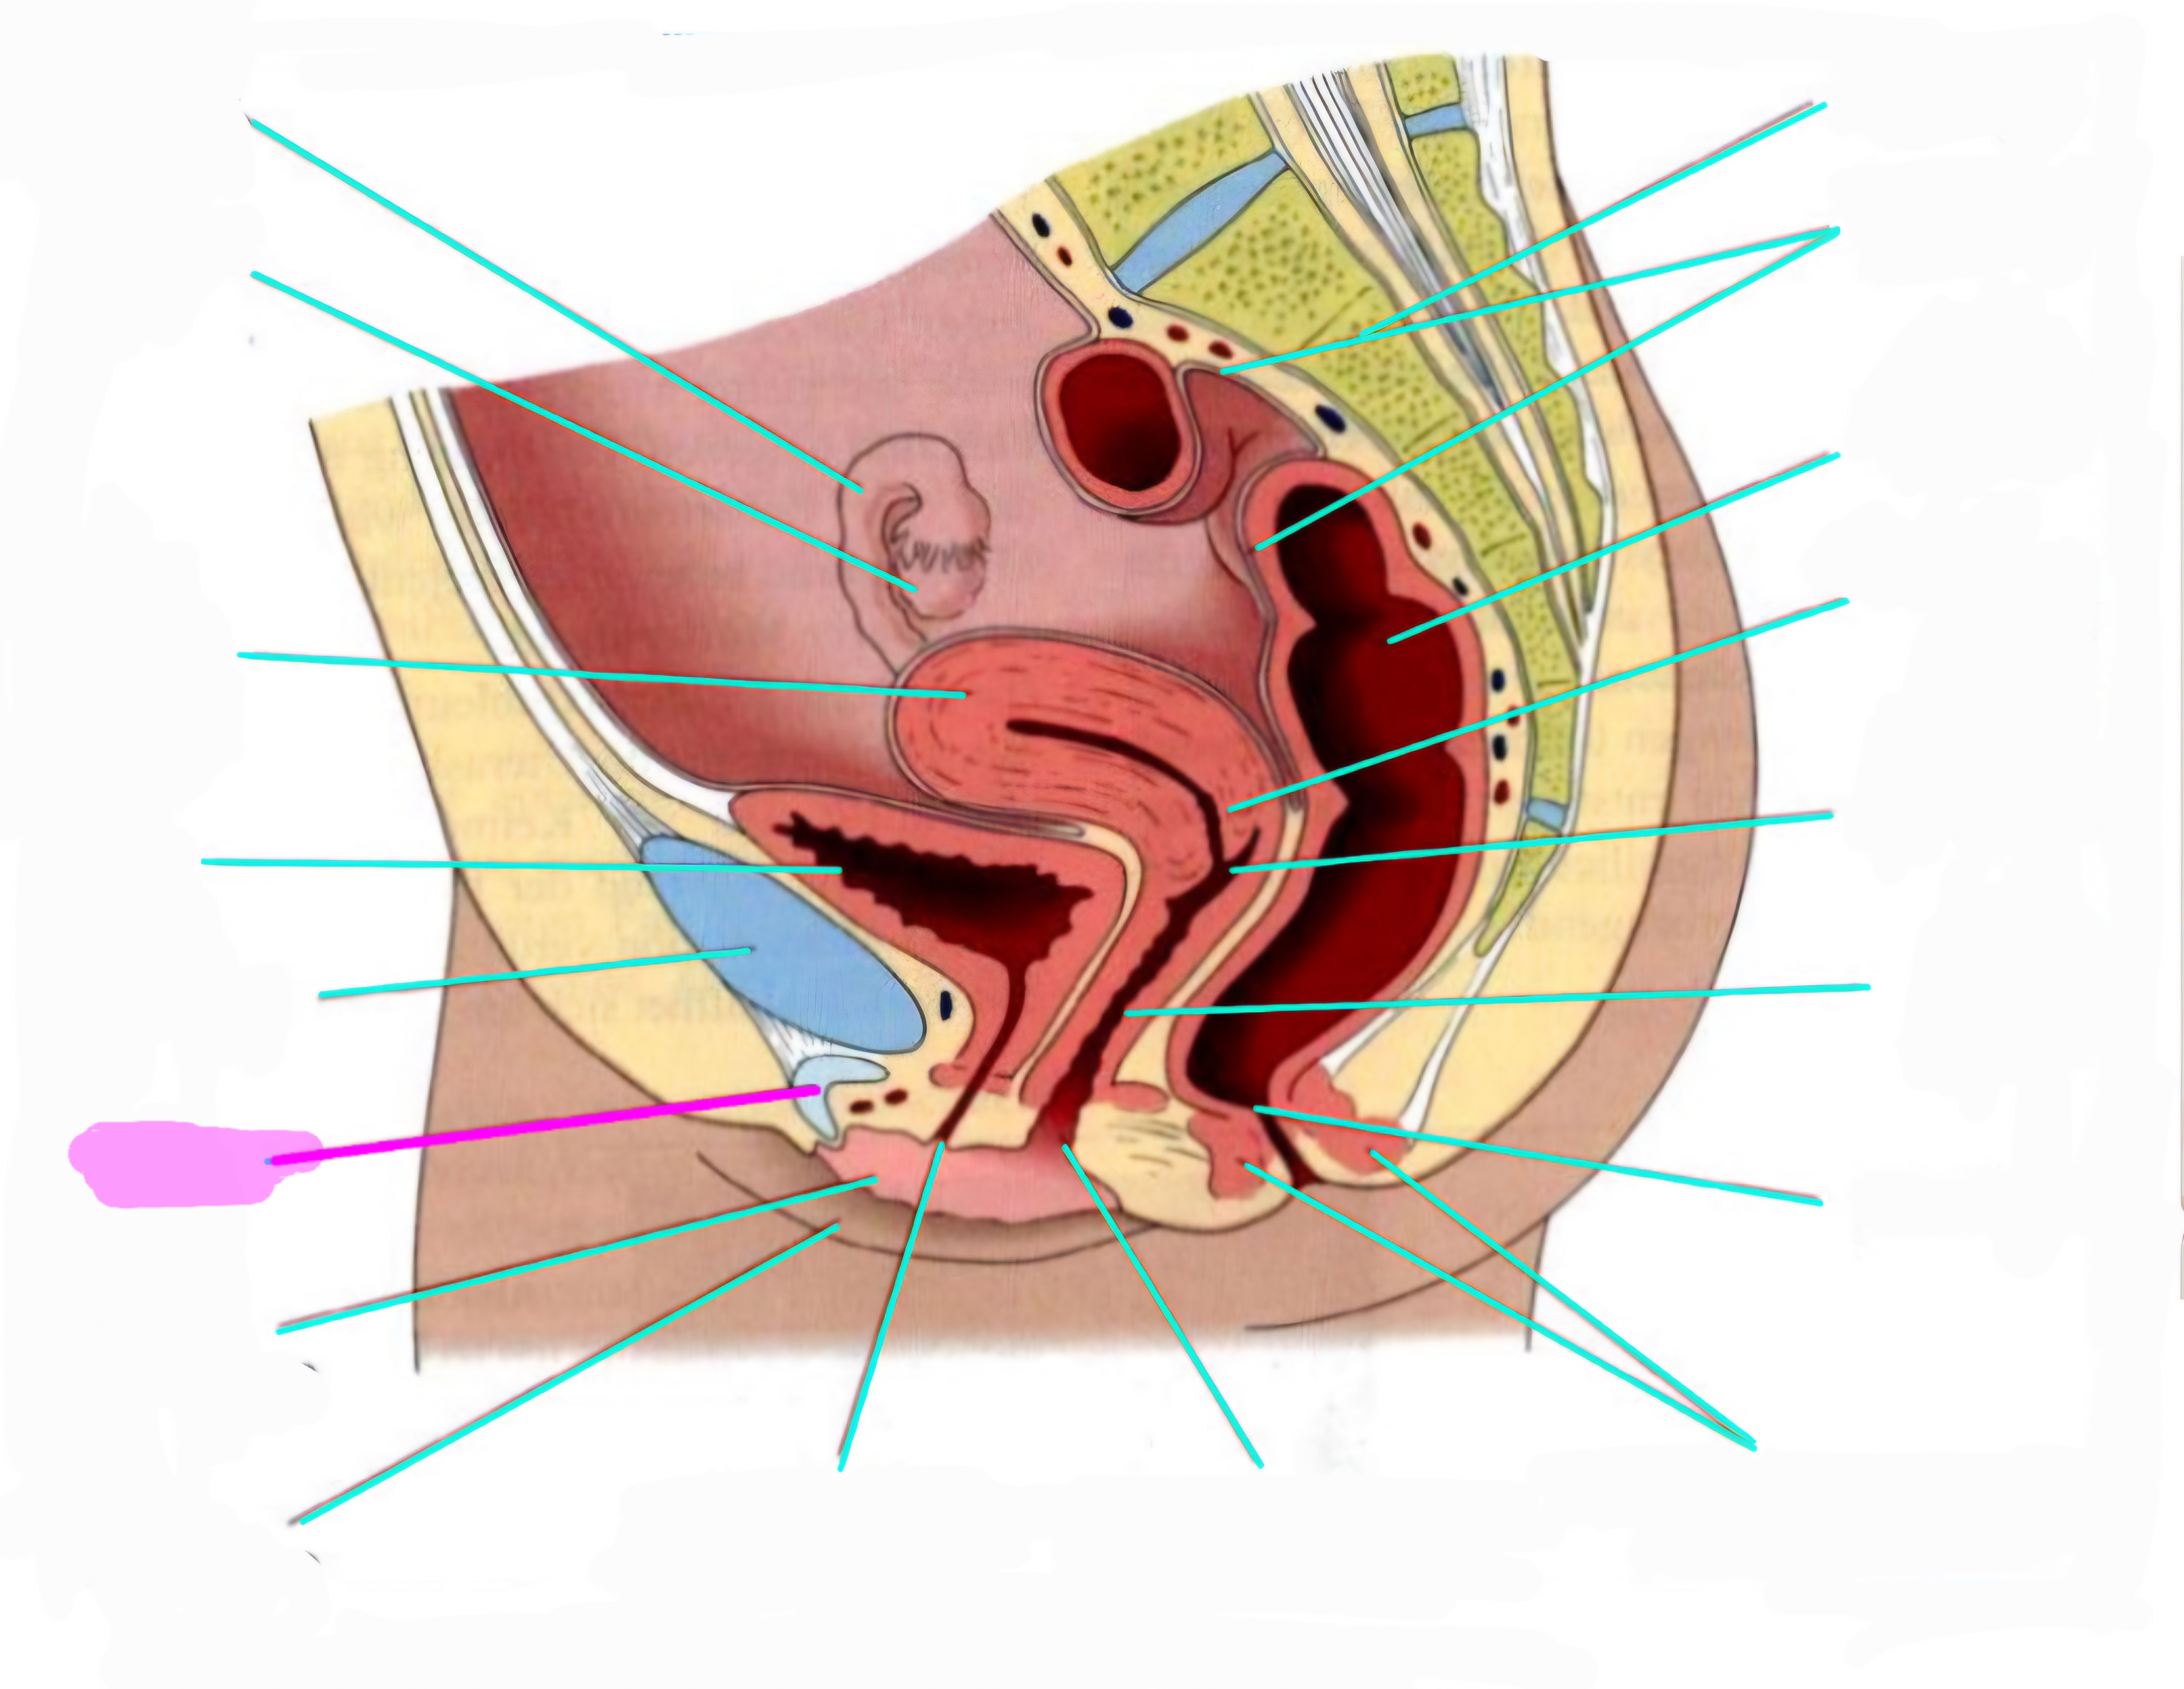

wbl. genital Anatomie

19 Terms

Tubea uterina (Eileiter)

Ovar (Eierstock)

Uterus (Gebärmutter)

Vesica Urinaria (Harnblase)

Symphyse

Klitoris

Labia minor pudendi (kleine schamlippen)

Labia Majoran pudendi (große Schamlippe)

Urethra (Harnröhre)

Introitus vaginae (Scheideneingang)

Sphincter ani externes (äußere Afterschließmuskel)

Anus (After)

Vagina (Scheide)

Portio (äußerer Muttermund)

Rektum (Mastdarm)

Zervix (Gebärmutterhals)

Peritoneum (Bauchfell)

Os sacrum (Kreuzbein)